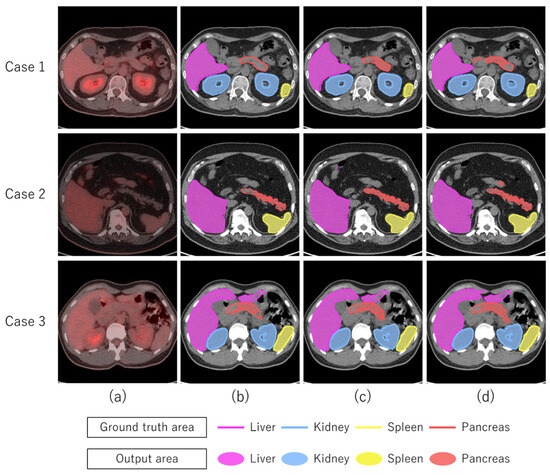

1.1. Related Works

3. Results

4. Discussion